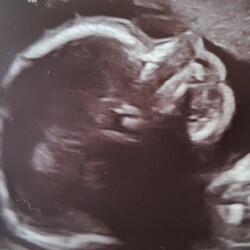

Ik heb geen last van emotie schommelingen of andere bijwerkingen. Afgelopen week de eerste echo gehad en de kleine deed het super!